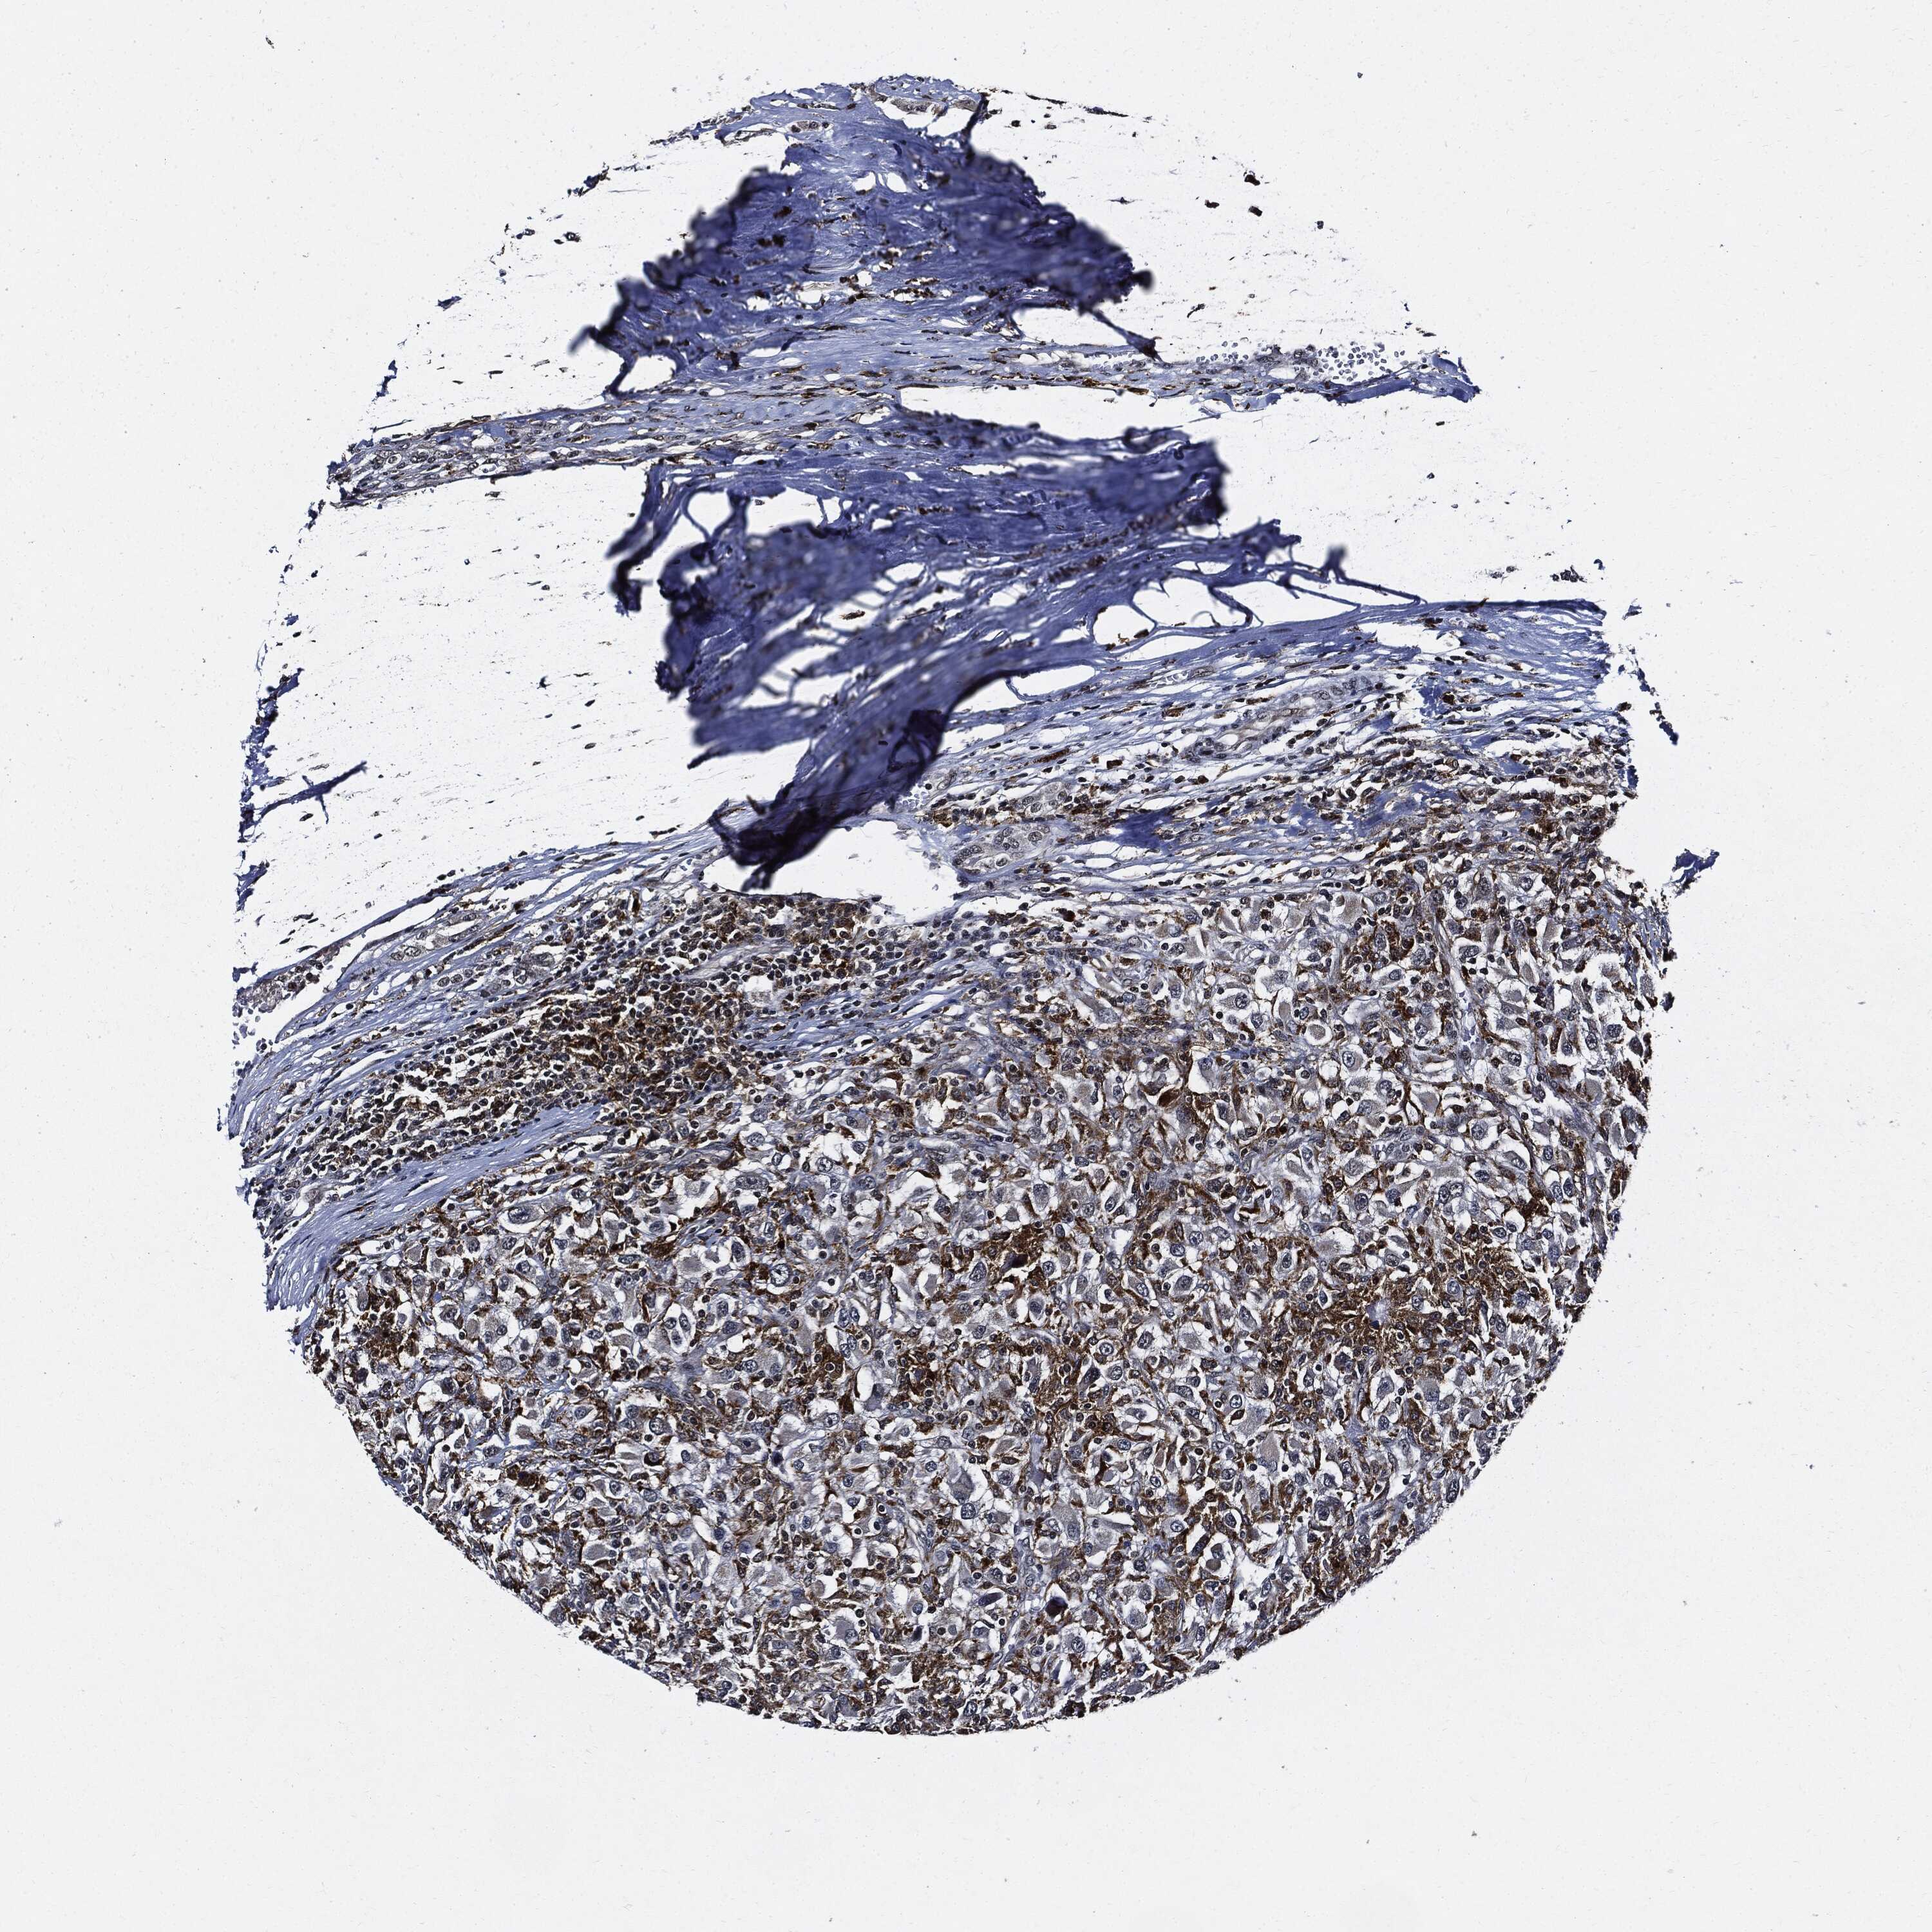

KIDNEY RENAL CLEAR CELL CARCINOMA (VALIDATION) - Interactive survival scatter ploti

The Survival Scatter plot shows the clinical status (i.e. dead or alive) for all individuals in the patient cohort, based on the same data that underlies the corresponding Kaplan-Meier plots. Patients that are alive at last time for follow-up are shown in blue and patients who have died during the study are shown in red.

The x-axis shows the expression levels (FPKM) of the investigated gene in the tumor tissue at the time of diagnosis. The y-axis shows the follow-up time after diagnosis (years). Both axes are complimented with kernel density curves demonstrating the data density over the axes. The top density plot shows the expression levels (FPKM) distribution among dead (red) and alive patients (blue). The right density plot shows the data density of the survived years of dead patients with high and low expression levels respectively, stratified using the cutoff indicated by the vertical dashed line through the Survival Scatter plot. This cutoff is automatically defined based on the FPKM cutoff that minimizes the p-score. The cutoff can be changed by dragging the vertical line or by entering a cutoff value in the square labeled "Current cut-off".

Under the Survival Scatter plot the p-score landscape (black curve; left axis) is shown together with dead median separation (red curve; right axis). Dead median separation is the difference in median mRNA expression between patients who have died with high and low expression, respectively. It is calculated as follows: median FPKM expression of dead patients with high expression - median FPKM expression of dead patients with low expression. This is intended to aid the user in visually exploring custom cutoffs and the associated p-scores and dead median separation.

Individual patient data is displayed and can be filtered by clicking on one or more of the category buttons on the top of the page. Categories describing expression level and patient information include: high, low, alive, dead, female, male and tumor stages. The scale of the x-axis can be toggled between linear and log-scale by clicking on the "x log" button. Mouse-over function shows TCGA ID, patient information and mRNA expression (FPKM) for each patient.

& Survival analysisi

Kaplan-Meier plots summarize results from analysis of correlation between mRNA expression level and patient survival. Patients were divided based on level of expression into one of the two groups "low" (under cut off) or "high" (over cut off). X-axis shows time for survival (years) and y-axis shows the probability of survival, where 1.0 corresponds to 100 percent.

SUGT1 is not prognostic in Kidney Renal Clear Cell Carcinoma (validation)

Best expression cut offi

Based on the FPKM value of each gene, patients were classified into two groups and association between prognosis (survival) and gene expression (FPKM) was examined. The best expression cut-off refers the FPKM value that yields maximal difference with regard to survival between the two groups at the lowest log-rank P-value. Best expression cut-off was selected based on survival analysis .

When clicking on this number, the vertical dashed line indicating cut-off, the interactive survival plot, and the Kaplan-Meier curve will be adjusted to show results based on the best expression cut-off.

: 32.05

Median expressioni

Median expression refers to the median FPKM value calculated based on the gene expression (FPKM) data from all patients in this dataset. When clicking on this number, the vertical dashed line indicating cut-off, the interactive survival plot, and the Kaplan-Meier curve will be adjusted to show results based on the median expression.

: N/A

Median follow up timei

Median follow up time refers to the median time (years) after diagnosis with this type of cancer, based on clinical data from all patients in this dataset.

P scorei

Log-rank P value for Kaplan-Meier plot showing results from analysis of correlation between mRNA expression level and patient survival.

N/A

5-year survival highi

5-year survival for patients with higher expression than the expression cutoff.

For melanoma and glioma, 3-year survival is shown.

5-year survival lowi

5-year survival for patients with lower expression than the expression cutoff.

TCGA RNA samplesi

RNA-seq data is reported as average FPKM (number Fragments Per Kilobase of exon per Million reads), generated by the The Cancer Genome Atlas (TCGA) .

Normal distribution across the dataset is visualized with box plots, shown as median and 25th and 75th percentiles. Points are displayed as outliers if they are above or below 1.5 times the interquartile range. FPKM values of the individual samples are presented next to the box plot.

Average pTPM 44.0

Number of samples 100